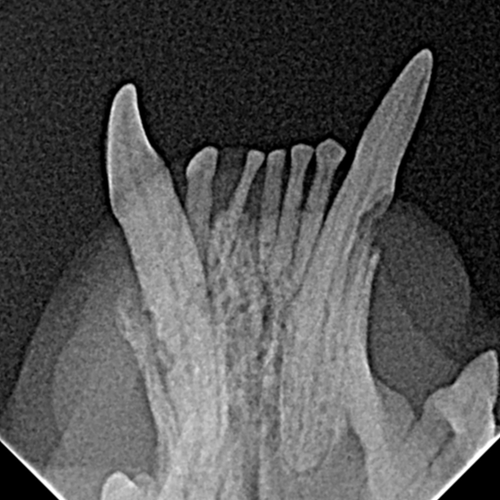

Fracture de l'os mandibulaire suite à une alvéolyse terminale lors d'une maladie parodontale de stade IV chez un chien